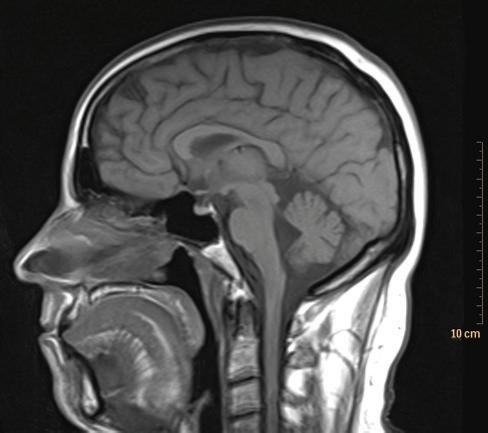

The presentation of lateral views is more complex and less consistent than the other projections. A traditional practice has been to orient lateral radiographs to match the position of the patient when the radiograph was made. An alternate practice that provides a more consistent viewing experience when radiographs are viewed with cross-sectional images is to match the common presentation of sagittal CT and MRI images (Fig 1-8). These are, almost universally, shown as if the anterior aspect of the patient is to the viewer’s left. This varies from the traditional practice of viewing sagittal ultrasound images, discussed later.

FIGURE 1-8 Sagittal MRI of the head and brain. Sagittal cross-sectional images, by convention, are presented as if the patient is facing the viewer’s left.